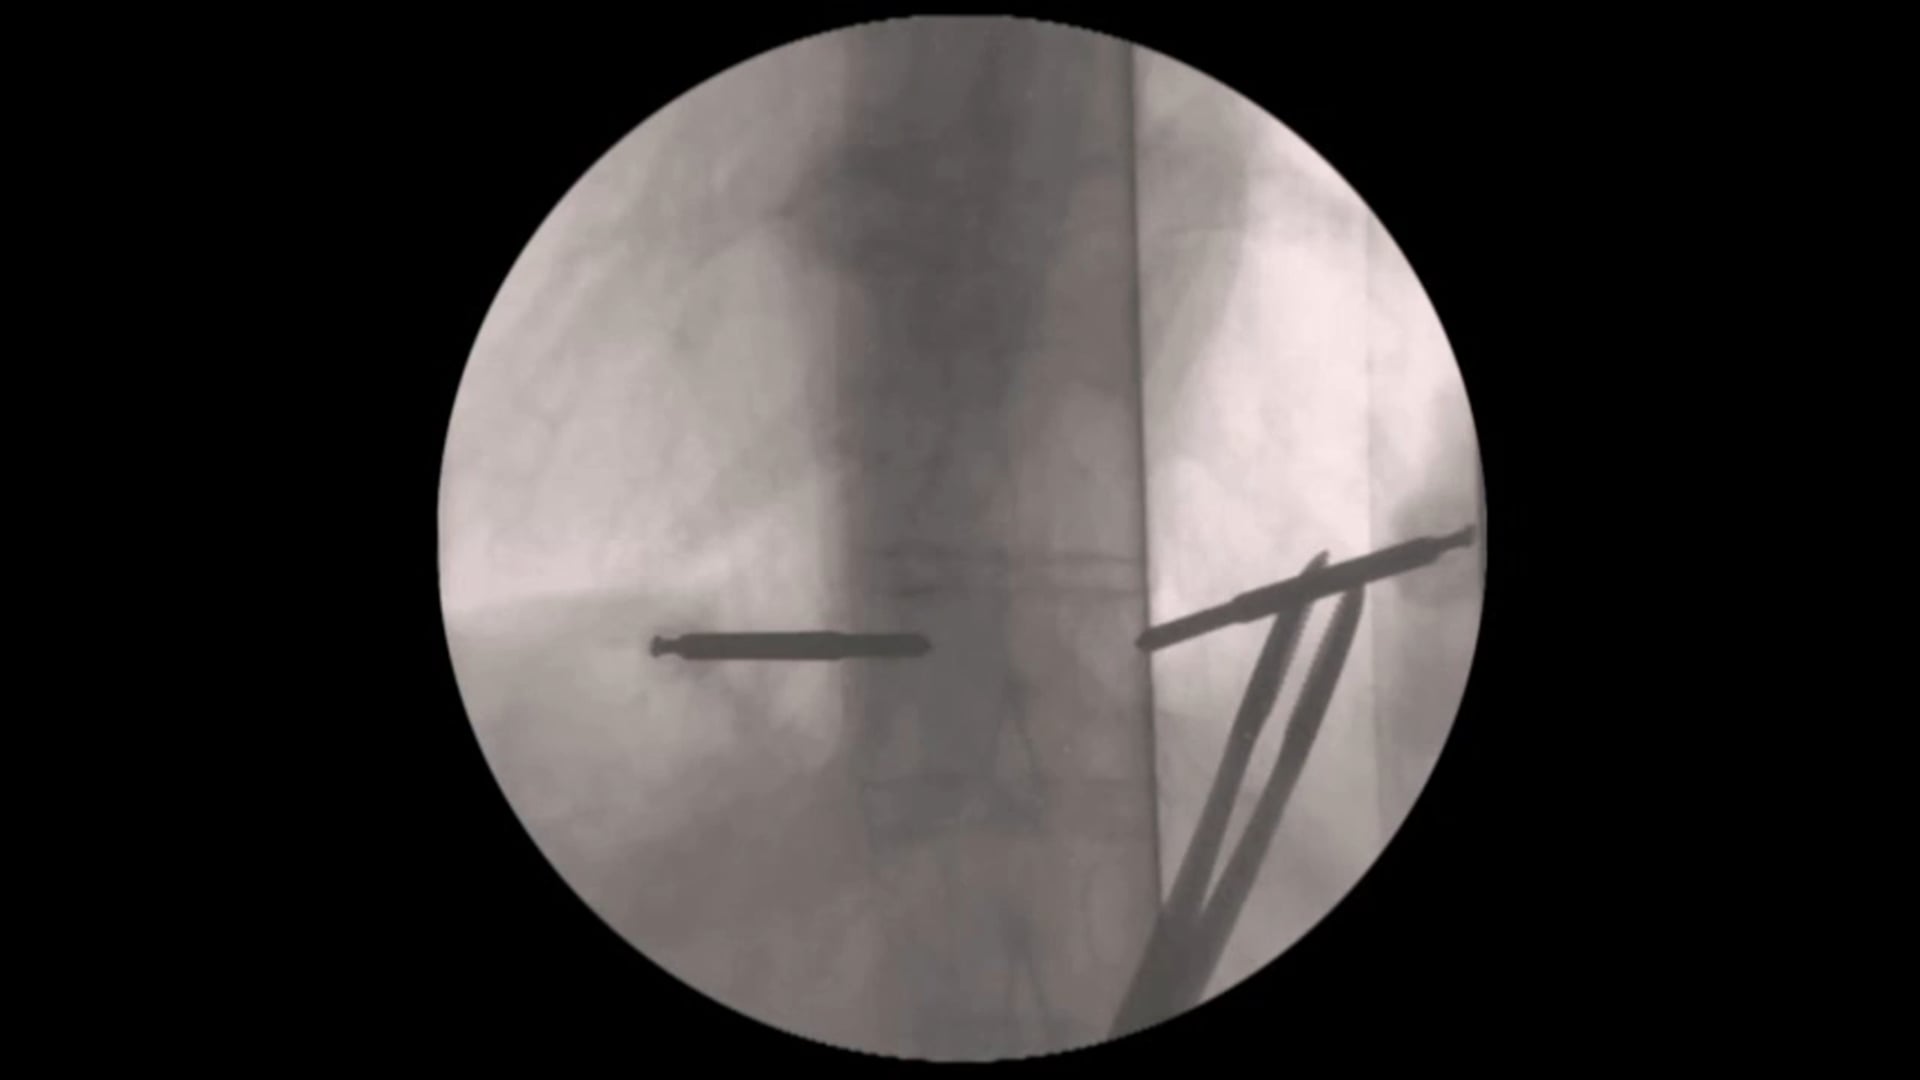

Trailer Percutaneous stabilization of a T9/10 fracture in a patient with anky...

Trailer Percutaneous stabilization of a T9/10 fracture in a patient with ankylosing spondylitis

Watch the full Video

Storzer Bastian MD

Schön Klinik München Harlaching

81547 München

GermanyProject 15-031

This video helps to understand the indication and technique of percutaneous stabilizatio...